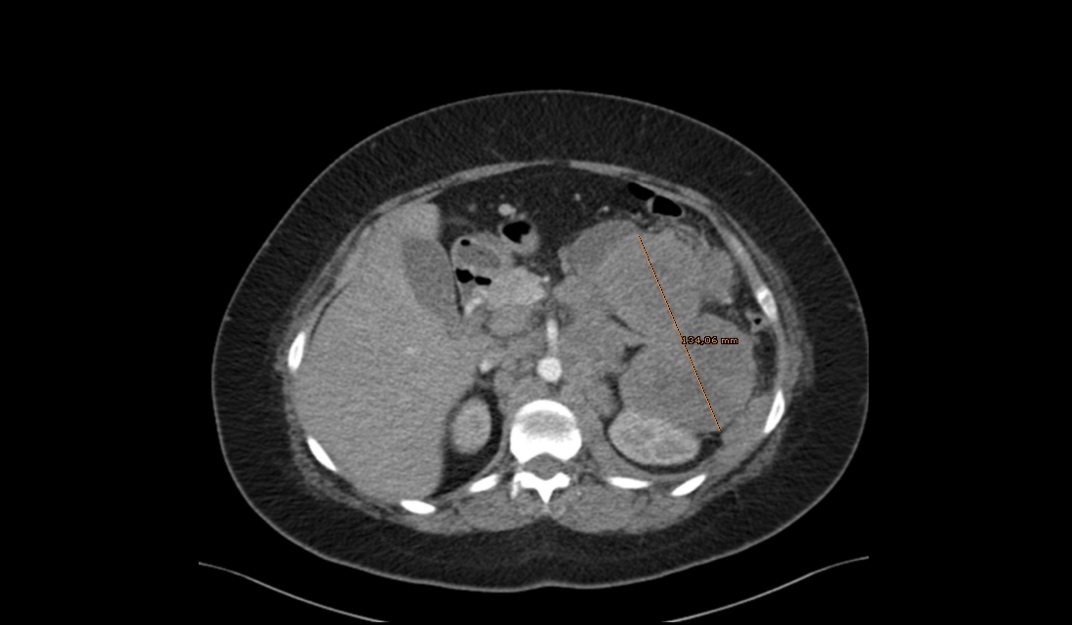

Se realiza analítica en urgencias que no mostraba datos de alarma y se solicitó ecografia abdominal que descartó patología abdominal aguda. Se decide completar estudio en urgencias con TAC que informa una tumoración sólida de 6,2x13cm en cola de páncreas que infiltra espacio perirrenal, en contacto con el bazo, arteria y vena esplénica con adenopatías retroperitoneales (Figura 1).

Figura 1. Corte transversal de TAC abdominal.